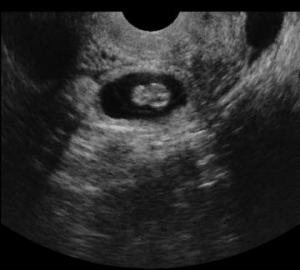

-ΥΠΕΡΗΧΟΓΡΑΦΗΜΑ(υπέρηχος):Μέθοδος εκλογής τόσο για την απεικονιστική διάγνωση όσο και για τη διαφορική διάγνωση της οξείας σκωληκοειδίτιδας.(ευαισθησία μεδόδου 86-96% και ειδικότητα 89-98%).

Υπερηχογραφικά η φυσιολογική σκωληκοειδής απόφυση απεικονίζεται στο 70% των παιδιών, είναι κινητή και ευπίεστη,δεν περιέχει υγρό στον αυλό της,έχει εγκάρσια διάμετρο 3-4χιλ και δεν εμφανίζει αιματική ροή κατά τον έλεγχο με έγχρωμο Doppler.Σε οξεία σκωληκοειδίτιδα, η σκωληκοειδής απόφυση είναι μη συμπιέσιμη και μη κινητή, έχει αυξημένη διάμετρο (μεγαλύτερη απο 6χιλ),πεπαχυσμένο τοίχωμα (πάχος τοιχώματος μεγαλύτερο από 3χιλ),πιθανή ασαφοποίηση και διακοπή της συνέχειας του βλεννογόνου,ενώ εντός του αυλού της παρατηρείται υγρό (άνηχο ή υποηχογενές περιεχόμενο με ίζημα).Πιθανόν να υπάρχουν λίθοι εντός αυτής (υπερηχογενή μορφώματα με συνοδό ακουστική σκιά).Ελέχγουμε επίσης και για πιθανές επιπλοκές, όπως ρήξη της σκωληκοειδούς,δημιουργία αποστήματος,περιτονίτιδα).